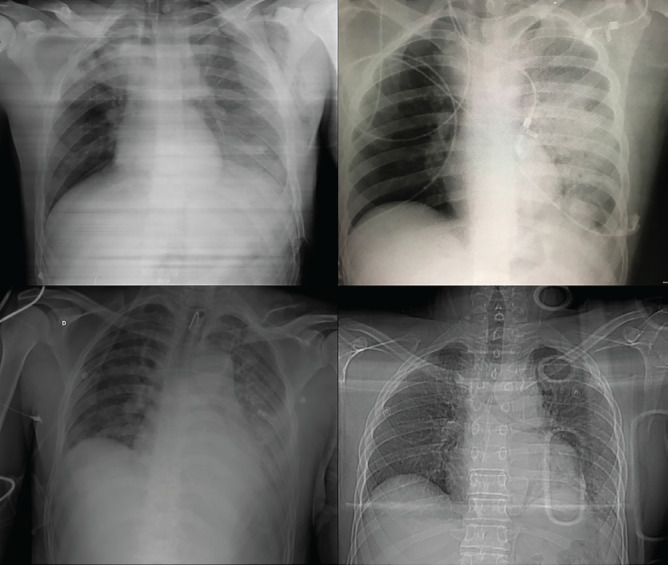

Results: All injuries were caused by high-energy traumas. Mean injury severity score was 38 and the revised trauma score was 6.58. A massive transfusion protocol was activated in 75.0% of cases. Diagnostic imaging showed varying accuracies, with computed tomography demonstrating superior sensitivity for both injuries. All TDH were left-sided posterolateral and BTAI predominantly involved the isthmus. Management followed a sequential approach, with 75.0% of diaphragmatic repairs preceding the aortic intervention. Mean hospital stay was 33 days, with complications including infections, deep vein thrombosis, and atelectasis. Despite the high severity of the injury, all patients survived.

Abstract Image